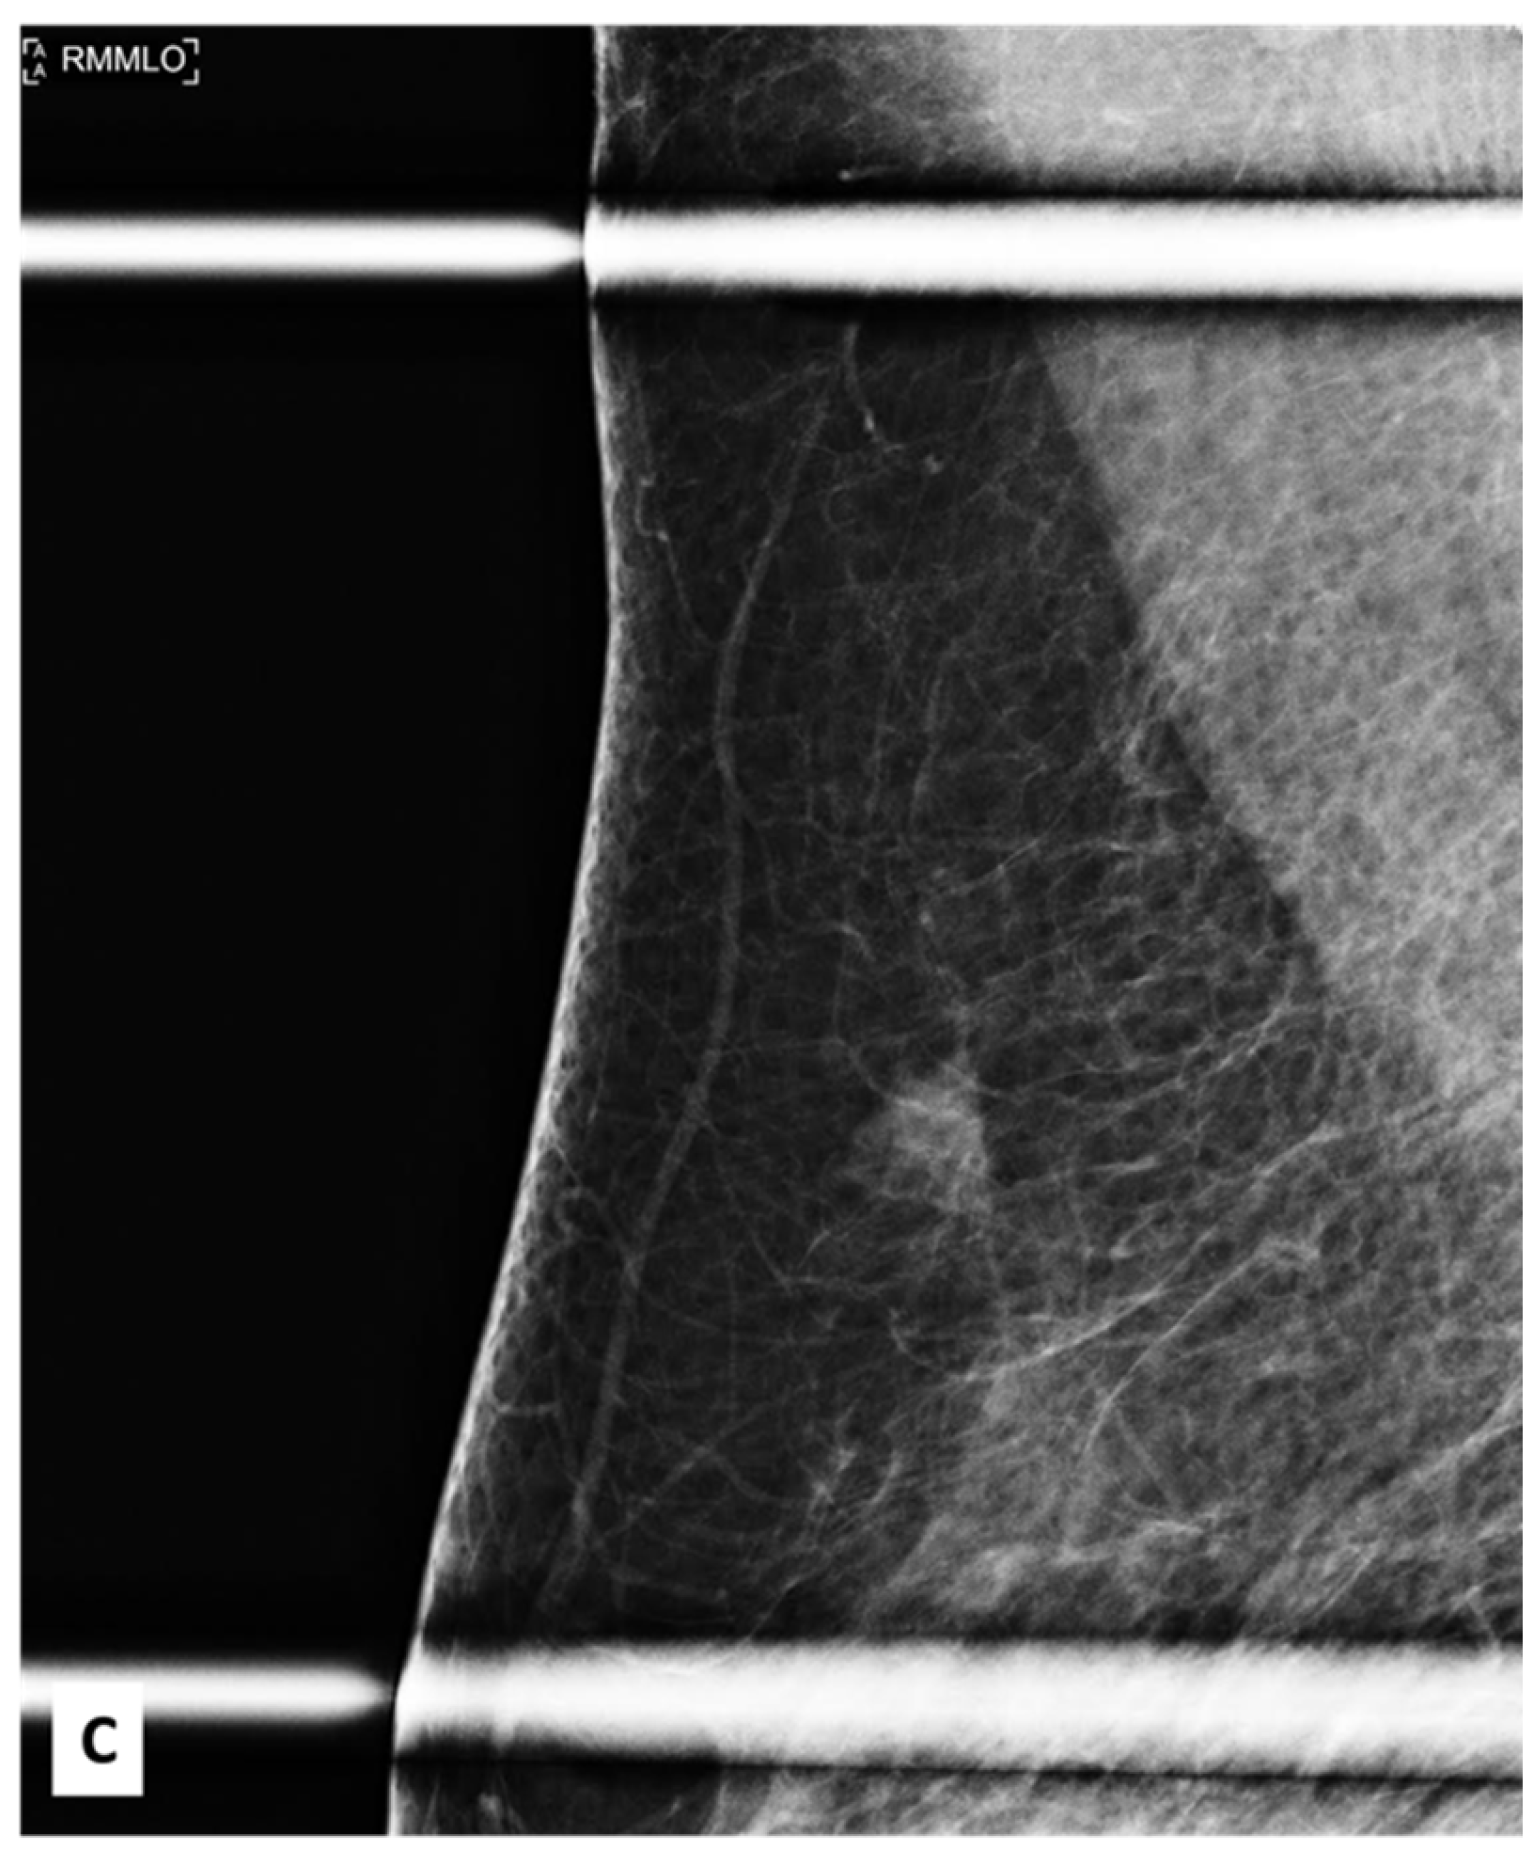

There was no indication of inflammation or swelling in either breast. A mammogram showed a large fat-containing oval-shaped lump with a circumscribed outline, and the mass in the upper outer quadrant of the right breast was approximately 9 cm from the nipple and measured 3 × 3.5 cm2 (Figure 2). However, mammography of the left breast showed nothing out of the ordinary. The subsequently targeted ultrasonography (US) revealed a heterogeneous isoechoic irregularly shaped solid mass that measured 3.3 × 3 cm2 and had eccentric cystic foci placed at the 9 o’clock position and approximately 8 cm away from the nipple (Figure 3). Differential diagnoses include phyllode tumor (PT) in addition to liposarcoma. The patient sought treatment at a tertiary hospital, where she underwent a right breast biopsy, and based on the findings of that procedure, a right lumpectomy without an axillary dissection was conducted. When seen under a microscope, the tumor was found to contain mature adipocytes, atypical spindle cells, and multivacuolated lipoblasts. All of these cell types were discovered to be embedded in a loose myxoid to fibrous stroma within the tumor itself. This information is provided by the pathology report. In addition, there were a significant number of regions that had pleomorphic cells, multinucleated, weird, enormous cells, and lipoblasts (Figure 4 and Figure 5).

Figure 2. Craniocaudal and mediolateral oblique nine-month follow-up mammography of the right breast. (A,B) A large, circumscribed fat-containing oval-shaped lump approximately 9 cm from the nipple measuring 3 × 3.5 cm2 (arrows) with no associated suspicious features (suspicious microcalcification or architectural distortion).